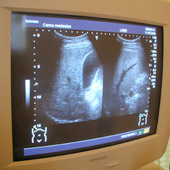

臨床検査技師とは

患者さんの血液や尿を検査し、その結果を医師に伝える仕事です。医師はこの結果をもとに患者さんの診断や治療を行います。